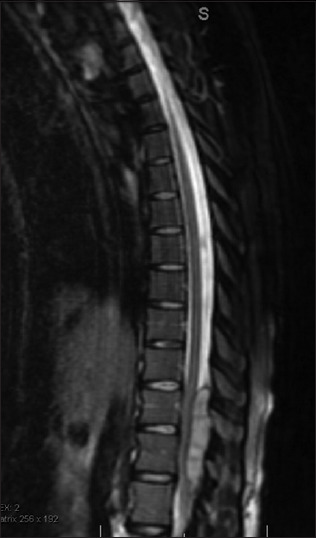

Pregnancy-induced changes to spinal anatomy and physiology can increase the complexity of neurosurgical intervention in this population. There are numerous reports focused on the neurosurgical management of intracranial pathology for pregnant patients. However, less is known about the neurosurgical management of acute spinal pathology. This study aims to discuss the management of emergent spinal pathology during late-term pregnancy. This is a case series of acute spinal pathologies in pregnancy. Epidural spinal needle fracture, epidural abscess, disc herniation causing an acute neurological deficit, and potential spine trauma. An extensive literature search relevant to the operative cases was performed to highlight the relevant themes to management. (1) The epidural spinal needle fracture was managed by surgical exploration under local anesthesia. (2) The epidural abscess was managed with laminectomy and surgical evacuation of the infective mass under general anesthesia. (3) The acute disc herniation was managed with laminectomy and discectomy under general anesthesia. All three examples were managed with emergent surgeries with improvement of symptoms. (4) The potential spine trauma was managed nonoperatively. Relevant similar cases from the literature review were summarized and strategies for management were outlined. Several factors such as anesthesia type, positioning, and operation sequencing must be considered when managing acute spinal pathology in late-term pregnant patients, necessitating multi-disciplinary input. However, effective management can result in successful surgical intervention and improvement of symptoms.